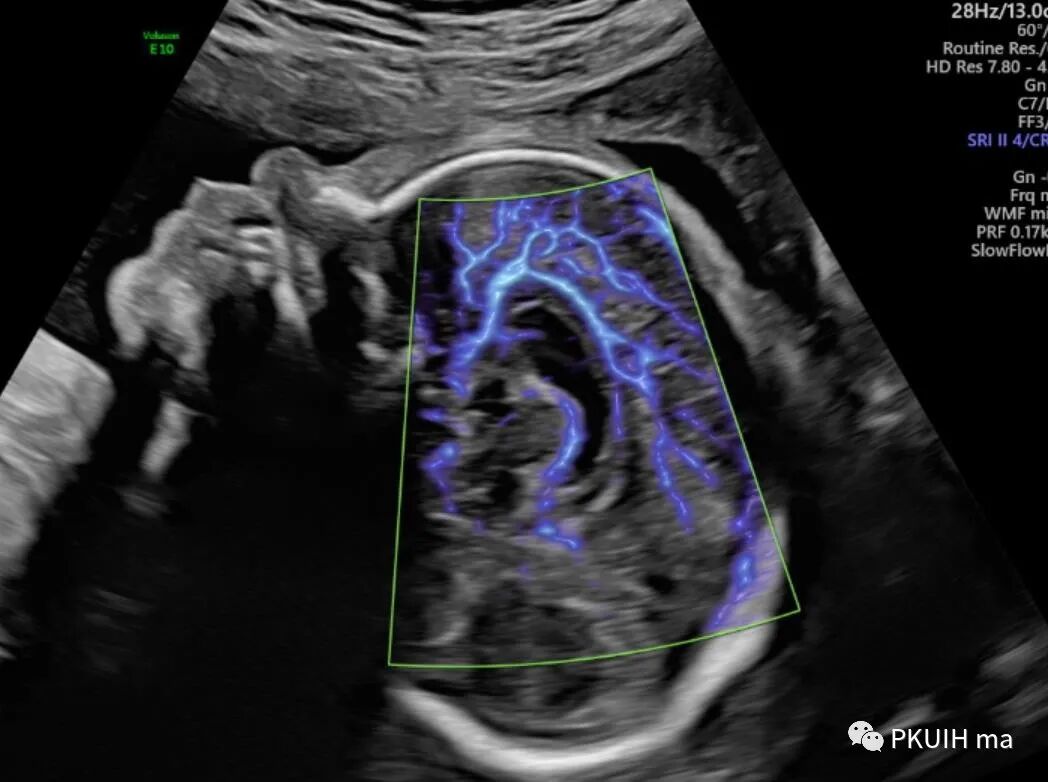

同样用这个功能我们可以很好显示胎儿胼胝体动脉及其分支,效果非常好,对于鉴别胼胝体发育有很大帮助。

另外我们可以采用各种渲染模式来显示胎儿大脑前动脉、胼周动脉及分支

另外我们也可以用此功能来显示胎儿颅内其他血管以及眼动脉和胎儿玻璃体动脉。